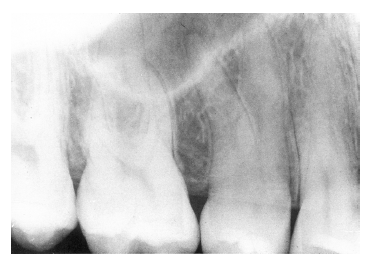

Figure 7 illustrates severe periodontal disease with extensive loss of alveolar bone around the tooth.

Figure 7 - Extensive Loss of Alveolar Bone

Figure 7